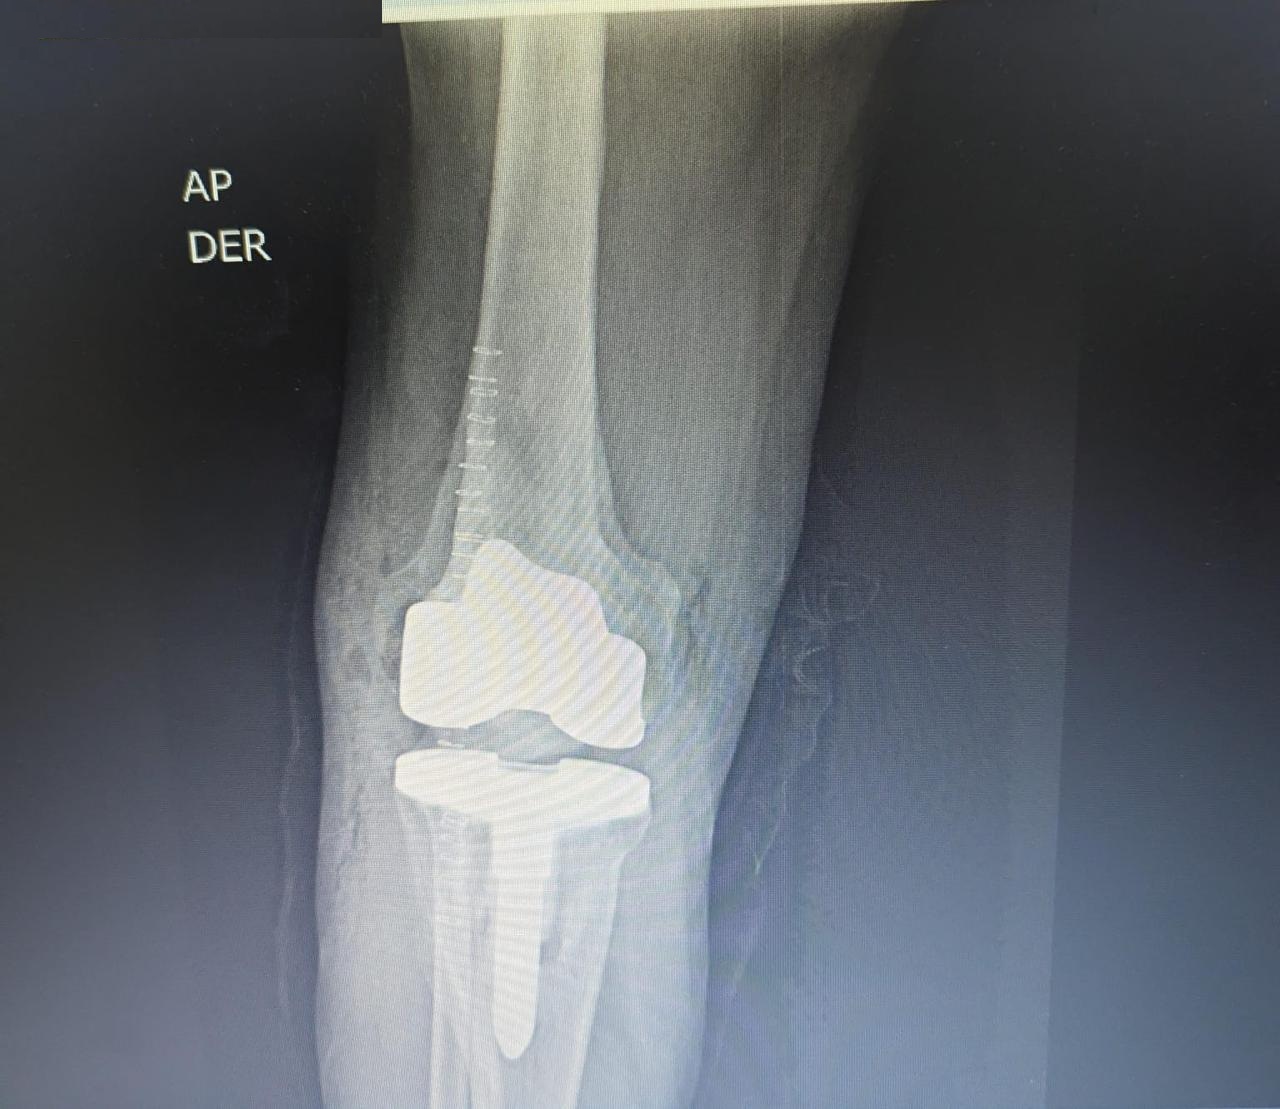

Antes Radiografía preoperatoria de fractura de tibia y osteoartrosis de rodilla

Después Radiografía postoperatoria de reemplazo articular de rodilla tras fractura de tibia

Traumatología

Reemplazo articular

Fractura de Tibia

• Perfil del Paciente: Masculino, 50 años.

• Historia Clínica: Antecedentes de 25 años de evolución con dolor crónico y pérdida de movilidad.

• Diagnóstico: Osteoartrosis secundaria a fractura de rodilla antigua.

• Resultado (Caso 2024): Intervención exitosa con recuperación completa. Actualmente el paciente presenta una evolución óptima y retorno a su vida cotidiana.